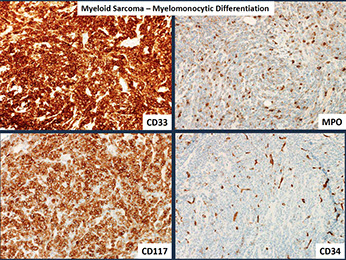

Myeloid sarcoma